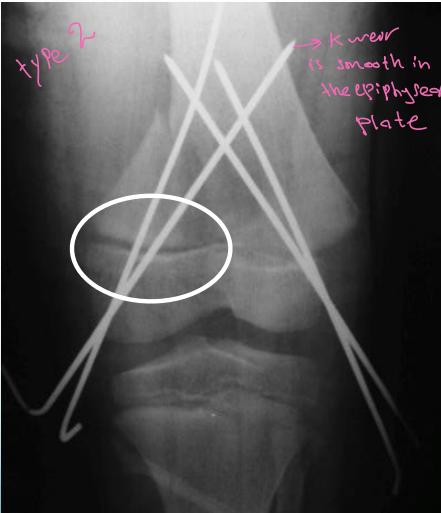

Classification – Salter-Harris

- Type II - Through the physis with small piece of metaphysis (75%)

Extra-articular (Type I / II)

- Unstable: K-wire / screws with cast

growth plate through epiphysis, not complete